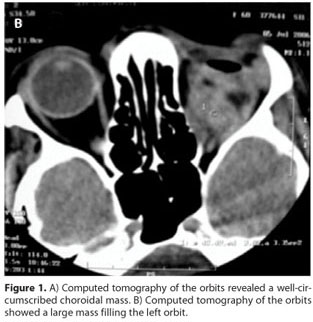

A 54-year-old woman presented to the outpatient ophthalmology department of our hospital in December 2005 with a 7-month history of progressive pain and decrease in vision in her left eye. She had been diagnosed with gastric adenocarcinoma 2 years previously and had undergone total gastrectomy. On presentation, her visual acuity was 20/25 in the right eye and light perception in the left eye. The intraocular pressure was within normal limits in both eyes. There was a relative afferent pupillary defect in the left eye. Anterior segment examination did not reveal any other abnormalities. Fundoscopic examination of the left eye revealed an elevated creamy yellow choroidal tumor infiltrating the macular area and extended around the optic nerve head causing swelling. The vitreous was clear. There was an exudative retinal detachment involving the macula. Ecography disclosed a mass with strong internal echoes in the same region, suggestive of a subretinal tumor. Computed tomography of the orbits demonstrated a large well-circumscribed subretinal mass (Figure 1A). The diagnostic impression on clinical and radiological findings was of a probable metastatic neoplasm. The right eye was unremarkable. Since investigations did not reveal metastasis at any other site, enucleation of the left eye was performed. The histopathological findings of the choroidal metastasis resembled the patient's primary tumor and were consistent with a moderately well-differentiated gastric adenocarcinoma. The patient refused radiation therapy or adjuvant systemic chemotherapy. Eight months after the enucleation, the patient was admitted with intense pain and edema in the left orbit. Computed tomography scan showed a diffuse irregular soft tissue mass involving in the left orbit (Figure 1B). An exenteration of the left orbit was performed without complications and the specimen was submitted to histological evaluation. Histopathological evaluation showed a highly cellular lesion (Figure 2). The cells were predominantly arranged in glands, follicles, and in small clusters and infiltrating tissue planes and vascular structures. On periodic-acid Schiff (PAS) staining, a PAS-positive mucinous secretory material was seen within the gland-like structures. These features were suggestive of a metastatic adenocarcinoma. A systemic work-up revealed multiple retroperitoneal lymph node metastasis and endoscopy showed an irregular narrowing of the esophagojejunal anastomosis, and recurrence of gastric cancer was diagnosed pathologically by biopsy. She was referred to the oncologist for possible palliative therapy. However, she elected not to pursue any form of treatment. The patient subsequently lost follow-up.